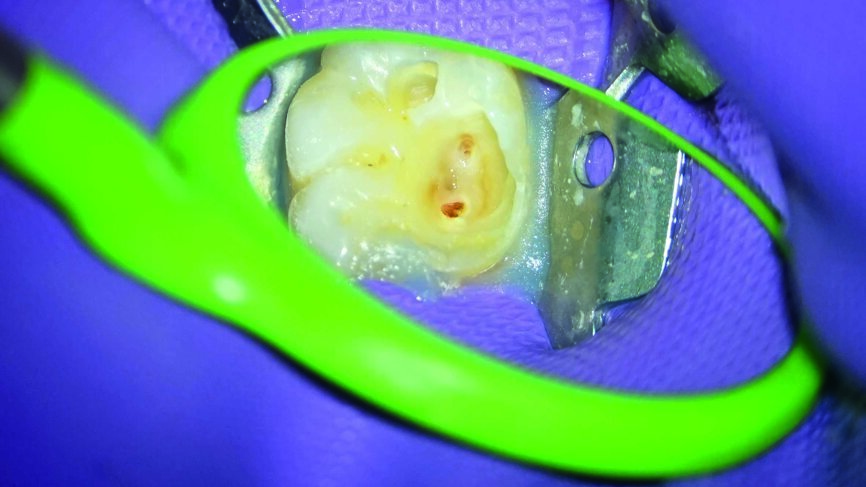

Ein 24-jähriger Patient kam mit vorübergehenden, provozierten Zahnschmerzen an Zahn #19 in die Zahnklinik (Abb. 1). Die Diagnose lautete reversible Pulpitis. Die Zahnfäule wurde unter kompletter Isolation entfernt, wobei es zweimal zur Freilegung der Pulpa mit minimalen Blutungen kam (Abb. 2). Die Blutungen wurden gestoppt, indem 10 Sekunden lang ein mit steriler Salzlösung getränkter Wattebausch auf die Stelle gedrückt wurde. Die Mundhöhle wurde mit 2,5% Natriumhypochlorit desinfiziert (Abb. 3), anschliessend wurde weißes MTA (Produits Dentaires) als Mittel zur unmittelbaren Pulpa-Überkappung eingesetzt (Abb. 4). Um sicherzustellen, dass das MTA korrekt eingesetzt wurde, kam das MAP-System für Dentalmaterialien (Produits Dentaires) zur Anwendung. Mit diesem System kann der Klinikarzt das Material exakt an der Expositionsstelle anbringen. Somit wird eine Verunreinigung der Dentinwände verhindert, die mit der Zeit eine Pigmentierung infolge des verwendeten Materials aufweisen könnten (Abb. 5 und 6). Sobald das MTA auf die Expositionsstellen der Pulpa und die tieferliegenden Teile des Pulpakammerdachs aufgetragen wurde, kam eine lichthärtende Kalziumhydroxidpaste zum Einsatz, um das Material zu schützen (Abb. 7), das Klebeverfahren durchführen und die abschliessende Zahnreparatur in derselben Sitzung vornehmen zu können (Abb. 8 und 9). Sieben Tage nach dem Verfahren war der Patient komplett symptomfrei und der Zahn reagierte normal auf Sensitivitätstests. In solchen klinischen Situationen ist davon auszugehen, dass zwischen sechs und neun Monaten nach dem Verfahren die Bildung von Kalkgewebe unter dem Überkappungsmaterial in Röntgenaufnahmen nachgewiesen werden kann. (7)